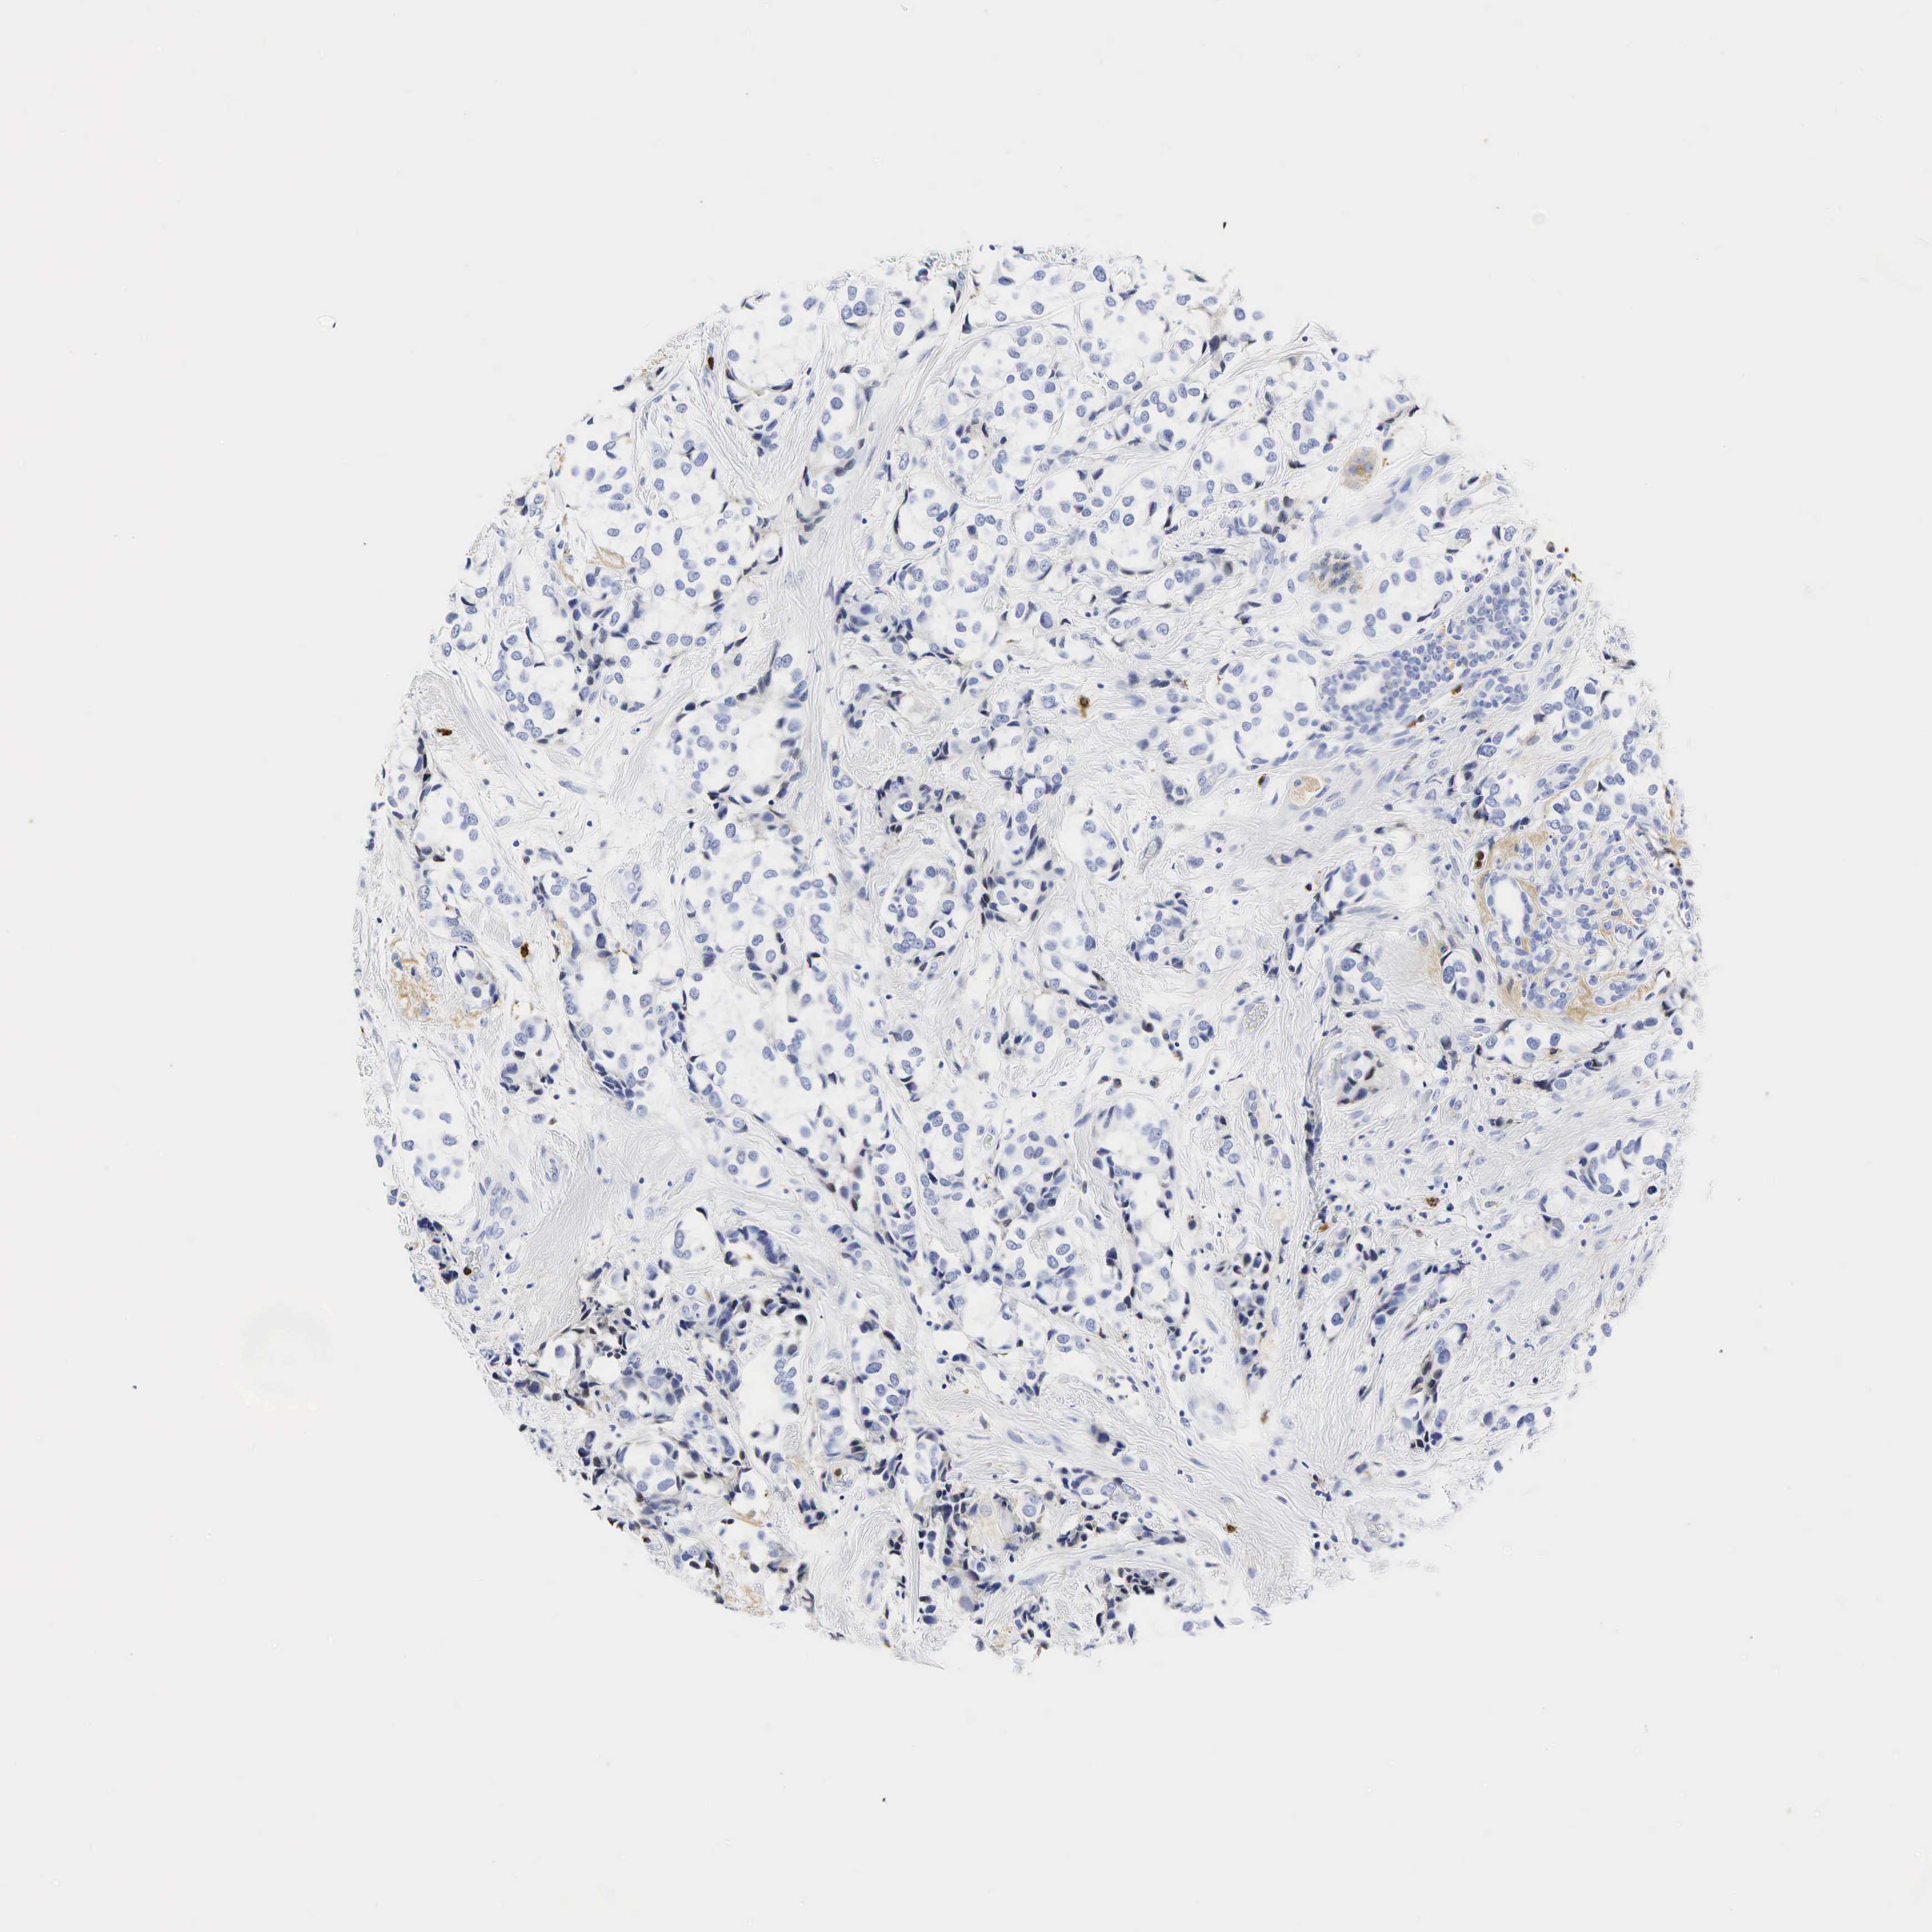

BRCA TCGA BRCA VALIDATION PROTEIN EXPRESSION

ANTIBODIES

AND

VALIDATION